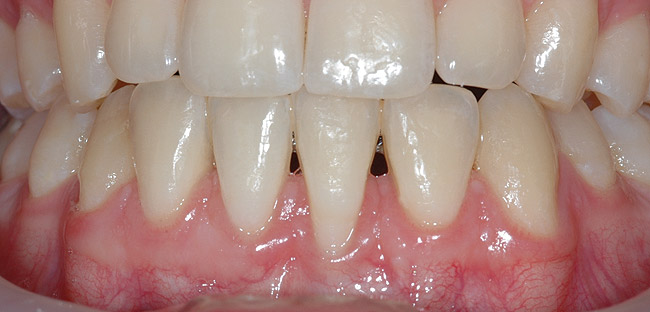

CASE 3 Fig 6. Post-orthodontic Miller Class II recession recommended for orthodontic treatment. Clinical view 5 years after orthodontic treatment showing a buccally displaced root of the lower incisor.

Figure 6

Fig 7. The CBCT sagittal view shows 4 mm tickness of bone on the lingual aspect of the affected tooth.

Figure 7

Fig 8. During orthodontic treatment showing a significant decrease of defect size.

Figure 8

In cases in which adequate lingual bone thickness (≥2.5 mm) is measured on CBCT, orthodontic retreatment should be encouraged (Figure 6 through Figure 8). Most of these patients present with a fixed orthodontic retainer bonded on the lingual aspect of the lower teeth. Therefore, the crown of the affected tooth is splinted and aligned relative to the adjacent teeth, while only the root is displaced toward the labial alveolar plate. Consequently, the orthodontic movement should consist of lingual root torque around a center of rotation placed in the crown. The torque can be easily achieved with rectangular wires or torqueing springs inserted underneath a heavy round base arch, which provides anchorage from the neighboring teeth.